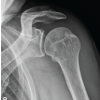

A 35-year-old male, daily wage labor belonging to low socioeconomic status, came with complaints of swelling and pain in his left forearm persisting for the past 5 months following an episode of generalized tonic-clonic seizure. His medical history was suggestive of generalized tonic-clonic seizure for which he was taking combined doses of lamotrigine and valproate as prescribed by his neurologist. Family medical history was significant for parents with similar seizure disorders. The patient had a history of recurrent ulnar fractures having experienced three previous surgeries. In previous instances, the patient underwent operative management with open reduction and internal fixation using a locking compression plate (LCP). He reported that he was working at a construction site where he had an episode of seizure and he fell down. His coworkers took him to the neurologist who intervened promptly and his seizure subsided. He was splinted with a plaster of Paris slab and had follow-up arrangement with the orthopedic surgeon. Instead, the patient’s father had previous surgical treatment with the corresponding author and scheduled follow-up 5 months after the injury. On physical examination, the patient was a 5’10”, 172 lb male with a healthy appearance. The left forearm was noted to have a swelling at the ulnar border of the middle forearm. The skin was intact. The patient had a sharp palpable gap at the mid-forearm region along with local tenderness. There was a notable decrease in pronation and supination compared to the unaffected limb. Neurovascular status was within normal limits. Radiograph of the forearm in anteroposterior and lateral views was performed which revealed a broken LCP with evidence of non-union at fracture site (Fig. 1). Basic blood investigations along with erythrocyte sedimentation rate and C-reactive protein were done. Given the diagnosis of aseptic ulnar diaphyseal non-union with implant failure, the treatment plan involved implant removal and re-fixation of the fracture site. The patient was admitted and after undergoing a thorough pre-operative workup by the anesthetist, he was posted for implant removal and re-fixation with LCP and bone grafting under interscalene block. The patient had a tourniquet applied to the left arm and inflated to 230 mmHg post-exsanguination using an eschmarch bandage during the procedure. We took a standard subcutaneous approach to the ulnar shaft using a straight incision across the non-union site. The plane was made between extensor carpi ulnaris and flexor carpi ulnaris. The implant and fracture site were exposed thoroughly. Implant was removed and the fracture site was assessed for vascularity. To our surprise, 3 cm of non-union site had no vascularity when assessed with drill holes for local signs of bleeding and so this part of ulnar shaft was removed (Fig. 2). We harvested non-vascularized fibula graft from ipsilateral lower limb (Fig. 3), placed it at the fracture site, and passed an elastic nail of 3 mm from olecranon passing through the graft and ulnar shaft (Fig. 4). Finally, a synthes long 10-hole 3.5 mm LCP plate was used and fixed in bridging mode using locking screws across the non-union site (Fig. 5). Four screws were put in proximal shaft, two in the graft site and four in the distal shaft of ulna. The fixation was supplemented with hydroxyapatite granules (G-Bone) (Fig. 6). The patient was kept under observation for 1 day post-surgery and discharged comfortably. The patient received first-generation IV cephalosporin antibiotic for 24 h. Postoperatively, during his stay at the hospital. Postoperatively, arm was protected in an arm pouch and physiotherapy in the form of gentle range of motion exercises was done for 3 weeks. Meanwhile, the patient continued his antiepileptic medications as prescribed by the neurologist. Regular follow-up at 1 month, 3 months, 6 months, and 1 year post-surgery was done. X-ray at final follow-up after 1 year revealed complete union at the fracture site (Fig. 7) with an acceptable range of motion as compared to the unaffected limb (Fig. 8).